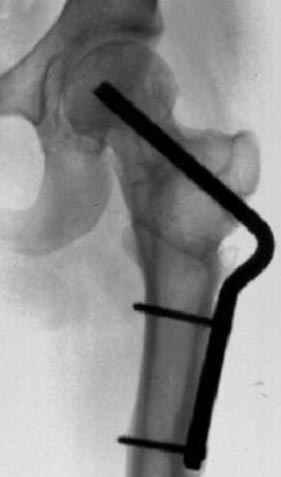

7:30 начало операции, больной на спине, попытка репозиции после анестезии N3, укладка больного на боку, доступ Kocher- Langenbeck, состояние седалищнего нерва около 2.5см кровоподтек, через joistick головка бедра приподнята, освобовождение сустава, фрагмент заднего края более 3х4 см репонирован на свое место. После промывания

сустава, репозиция вывиха (N4), фиксация фрагмента 2.7(4) мм шурупами и допольнительно реконструктивной пластиной на 8 дырок, фиксация 3.5мм шурупами проксимально и дистально.

Интраоперционные N5 косая запирательная и N6 подвздошный снимок

11:50 больной в послеоперационной, рентгенограмма N7, компьютерная томограмма в тот же день N8-10